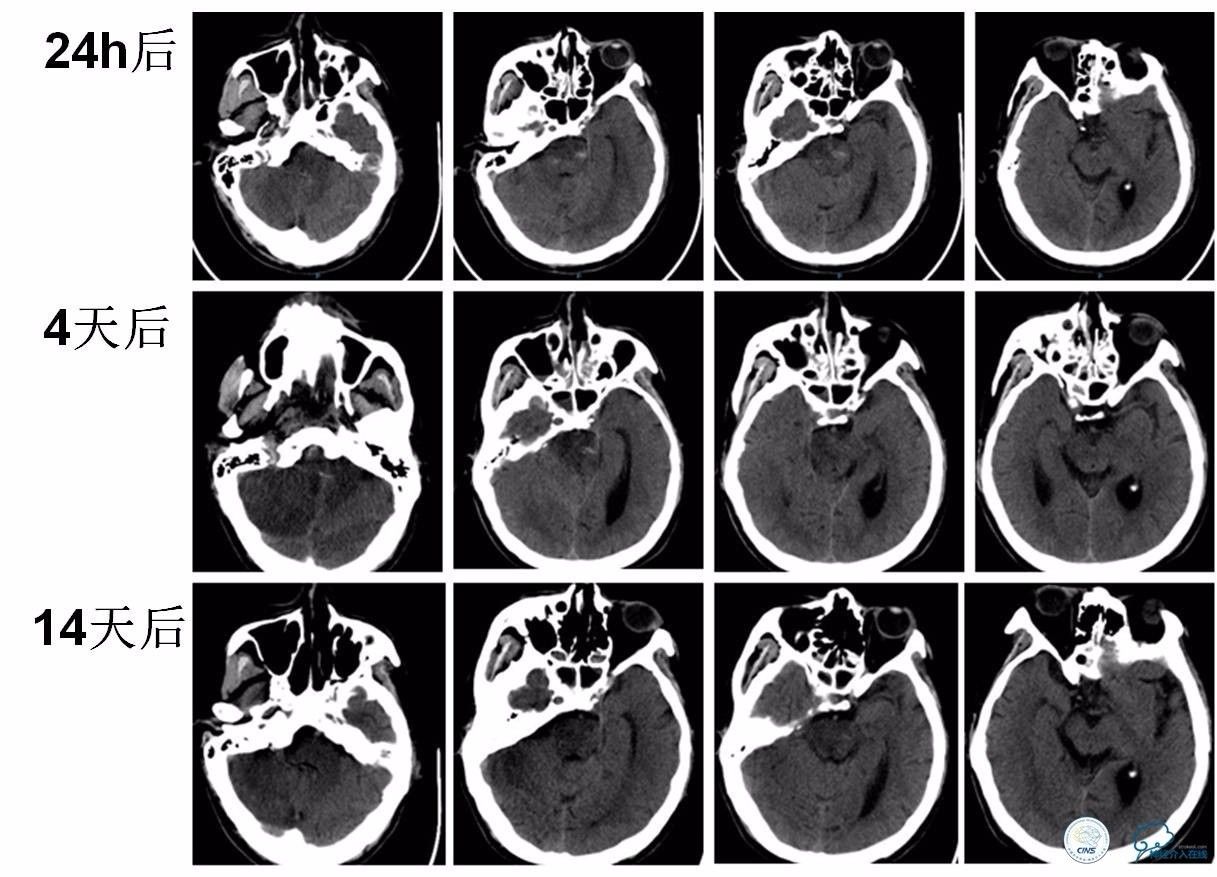

★术后24小时、术后4天、术后14天复查头颅CT。